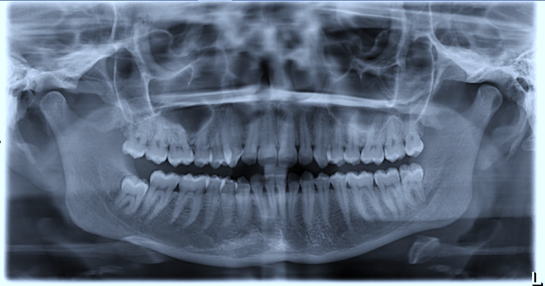

Tooth 4.8 is planned for extraction. Which radiographic findings suggest an increase in the degree of difficulty of the extraction?

Tooth 2.8 is planned for extraction. Which radiographic findings suggest an increase in the degree of difficulty of the extraction?

Tooth 1.8 is planned for surgical extraction. Which radiographic findings suggest an increase in the degree of difficulty of the extraction?

Tooth 2.8 is planned for surgical extraction. Which radiographic findings suggest an increase in the degree of difficulty of the extraction?